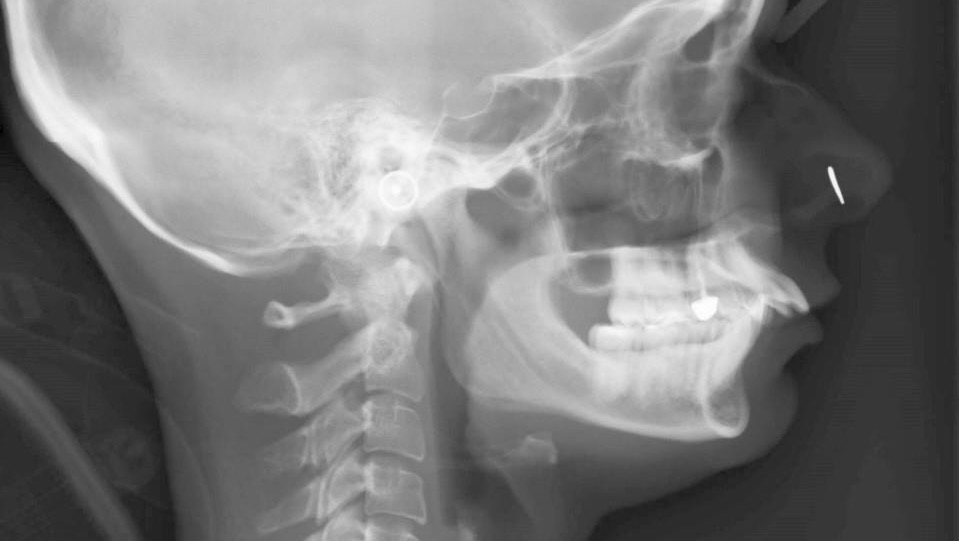

Pre braces xray: